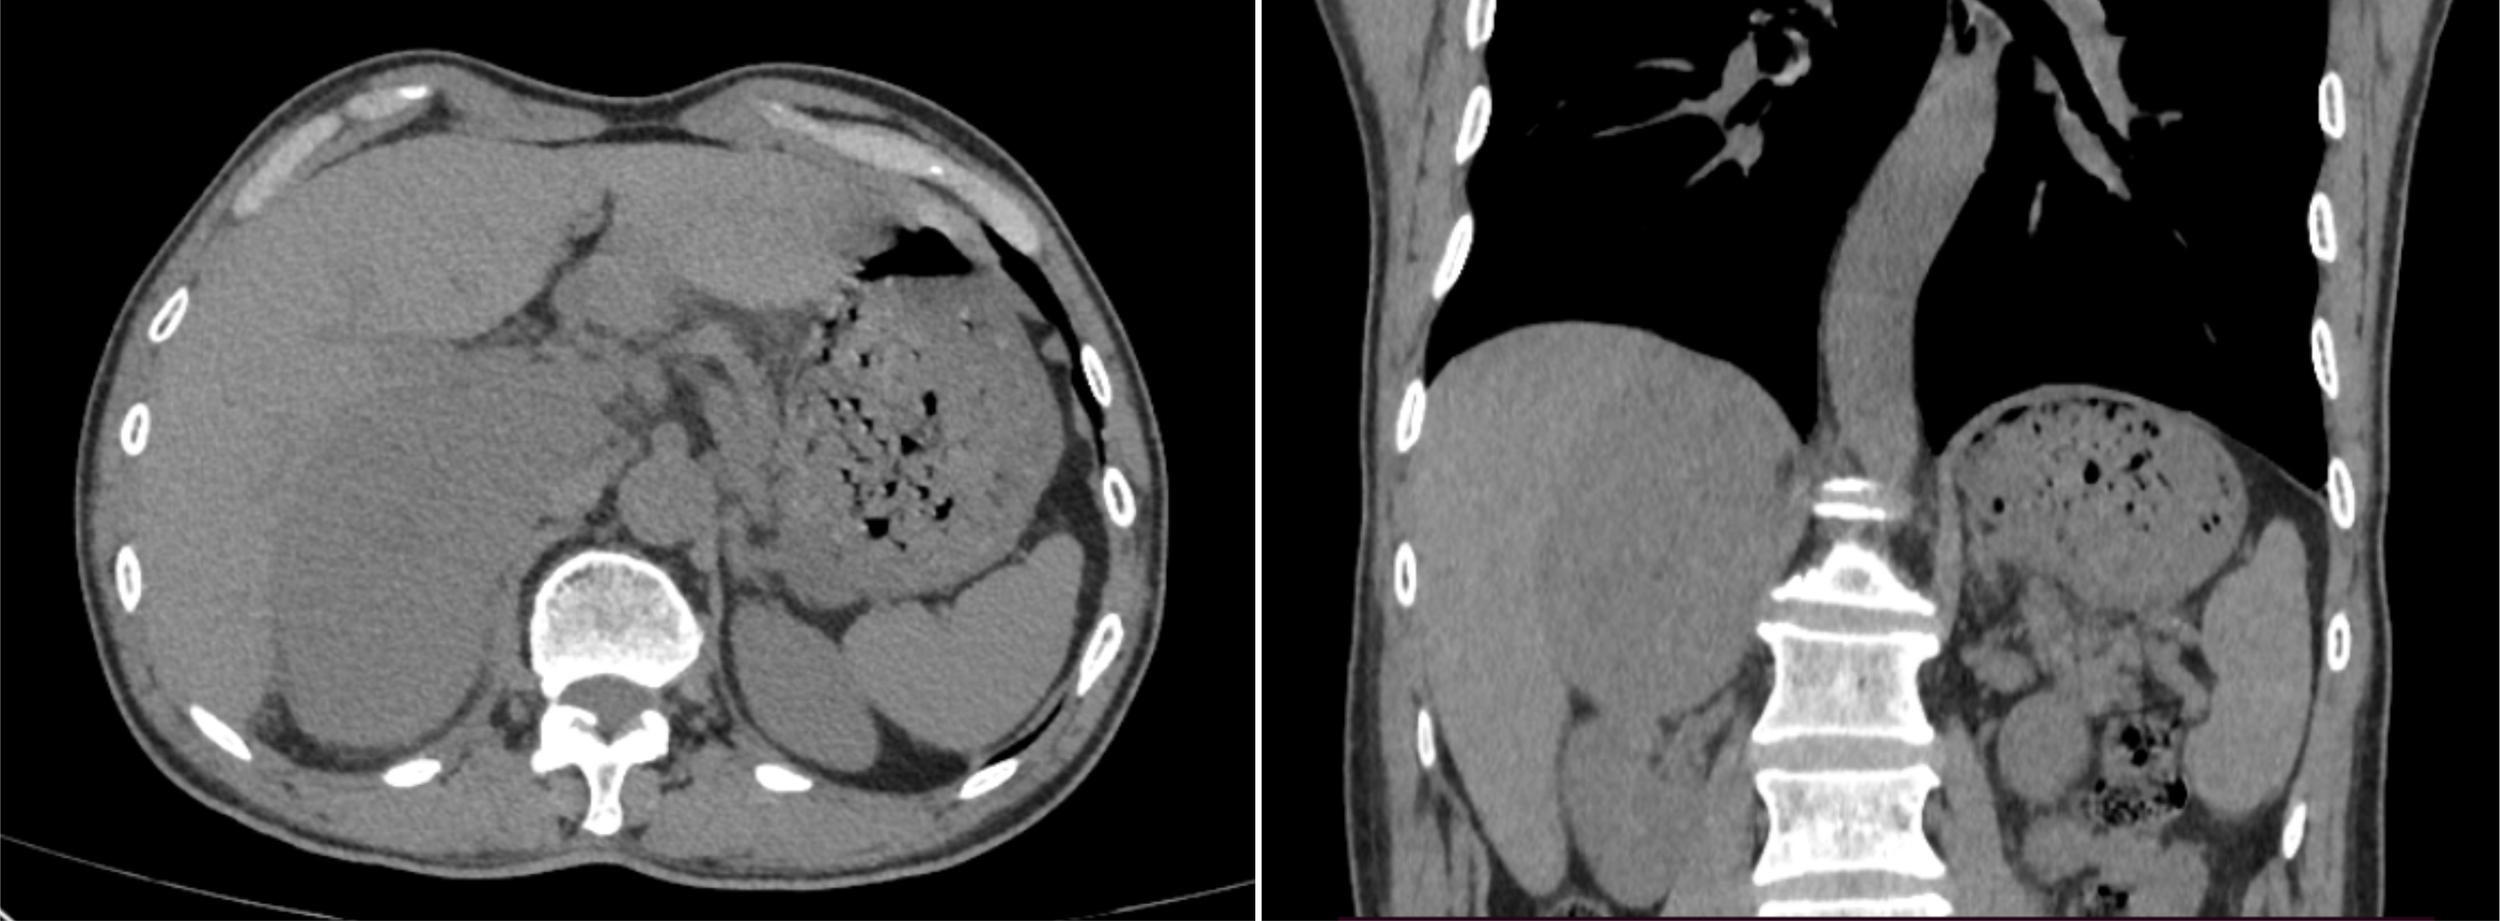

Figure 1 Selected window images of axial, coronal plain abdomen CT scan soft tissue demonstrating a heterogeneous adrenal mass measuring 10.6×6.4×11.0cm, which abutted and compressed the liver parenchyma, right renal and IVC.

A 69-year-old man with an incidental right adrenal gland mass was admitted to our institution. He had no relevant past medical history, and no family history was identified. Hematological examination did not reveal any abnormal findings. Adrenal function laboratory assay indices were normal, including cortisol, catecholamine and aldosterone. Initial CT scan revealed a round-like, well-defined slightly hypodense lesion in the right adrenal gland region measuring approximately 10.6×6.4×11.0 cm in size, with a CT value of about 34 HU. The right posterior liver, portal vein and upper pole of the right kidney were displayed (Figure 1). Right adrenal gland imaging was not conclusive. A follow-up MRI (Figure 2) revealed a 10.2×6.5×10.5 cm oval tumor in the right suprarenal region, with a high-low mixed sign on T1WI and slightly high signals on fat suppression T2WI sequence. A central scar was noted in the lesion, which was hypointense on T1WI and T2WI. Upon enhancement scan, the lesion exhibited a slight to moderate heterogeneous enhancement with no enhancement in the central scar. Visualization of the right adrenal gland was not clear. There were no significant enlarged lymphnodes or metastatic foci. Gene detection and FDG PET/CT were not carried out due to economic reasons.

For our case, the mass was detected during physical examination, without obvious clinical manifestations. In a review of previous CT imaging in 2019, no adrenal mass was found, indicating rapid progress. Reports on MRI and CT of proximal ES involving uterine body, cervix and renal have been relatively few. To date, four cases of primary adrenal epithelioid sarcoma have been reported, but imaging features were not mentioned (3–6). A typical CT of proximal ES reveals slightly lower or equal density mass in homogeneous enhancement on enhanced scan. For the larger, manifestations include tissue invasion, hemorrhage and necrosis, but it is rarely to find calcification (7). On MRI, proximal ES is usually homogeneous in signal, isointense or hyperintense in T1WI and T2WI, and homogeneous or heterogeneous enhancement, with no enhancement in the necrotic area. There is infiltration to adjacent tissues or bones in some cases (8). In our case, plain CT revealed a slightly low-density mass in the right adrenal gland. Upon MRI, the mass exhibited heterogeneous isointensity in T1WI and relative hyperintensity with hypointensity central scar inside in fat-suppression T2WI. The mass had hyperintense signals on DWI and hypointense signals on the ADC map, while the central scar presented hypointensity. After Gd-DTPA enhancement scanning, it also showed progressive and slight to moderate enhancement on fat-suppression T1WI, with no enhancement of the central scar. The CT findings were comparable to those reported earlier. Due to the small number of reported patients, characteristic imaging findings should be investigated further for comprehensive understanding of the disease. A summary of clinical characteristics and imaging findings of the four reported cases of primary adrenal ES are listed in Table 1.